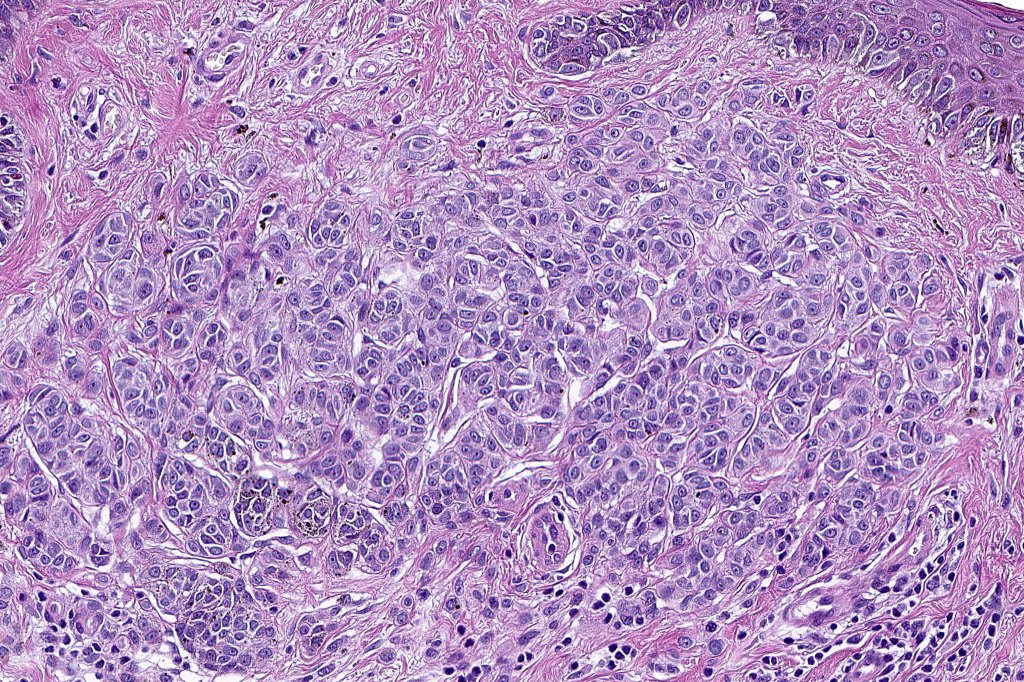

•Architectural disorder- lentiginous and nested, nests abnormally located (at the sides of the rete ridges & overlying the dermal papillae in addition to the tips of the rete ridges rather than solely occupying the tips of the rete ridges as is seen in banal nevi), horizontal orientation & bridging between junctional nests (this should not be confused with bridging between adjacent rete ridge squamous epithelium)

•In compound lesions, the nest size should be smaller than the junctional ones and the degree of atypia the same or less

Dysplastic nevus in the majority of cases is instantly recognizable, often at low power. The most important differential diagnosis is obviously melanoma. In junctional lesions, widespread/uniform high grade atypia, frequent mitoses and Pagetoid spread are indicative of in situ melanoma. In compound lesions, dermal nests larger than junctional ones, expansile dermal nests, severe atypia and mitotic activity indicate the presence of melanoma